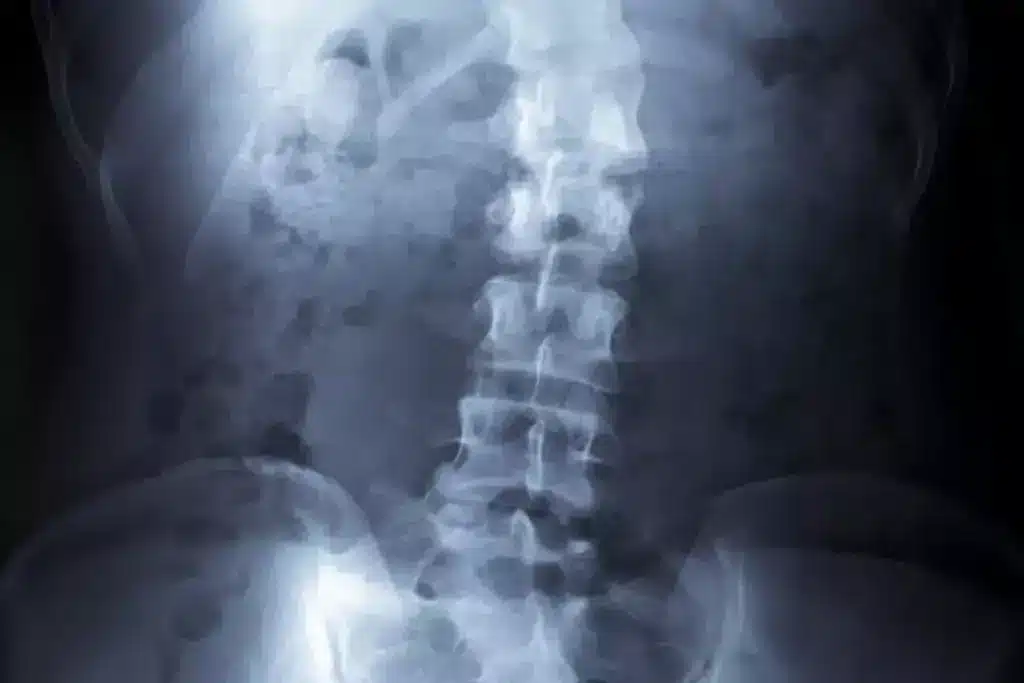

Imaging Methods for Scoliosis

Imaging studies are vital for confirming scoliosis and measuring the spinal curvature. The main imaging methods are:

- X-rays: X-rays are the most common method. They give a clear view of the spine’s alignment and curvature.

After diagnosing scoliosis, measuring the curvature is key. The Cobb angle is used to measure the curvature on X-rays. It’s calculated by drawing lines on the X-ray and measuring the angle formed.